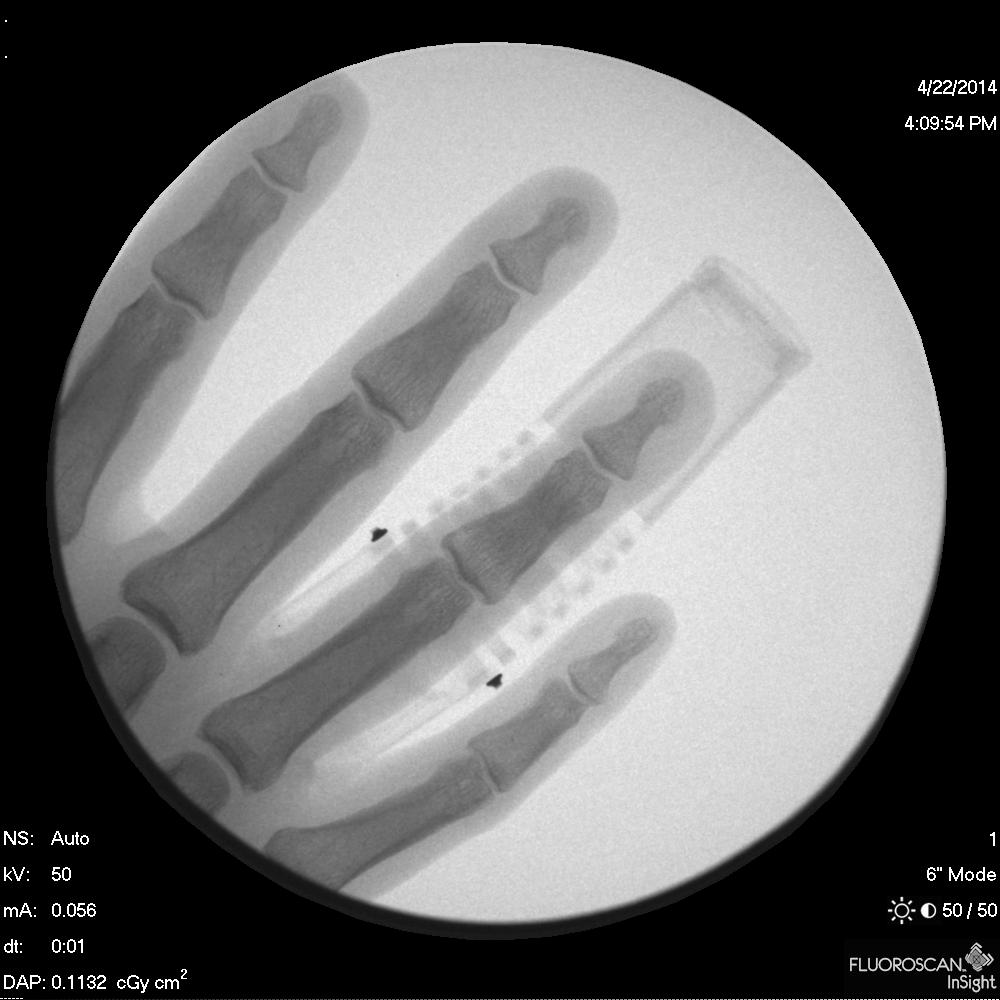

bend, a revolutionary medical finger split